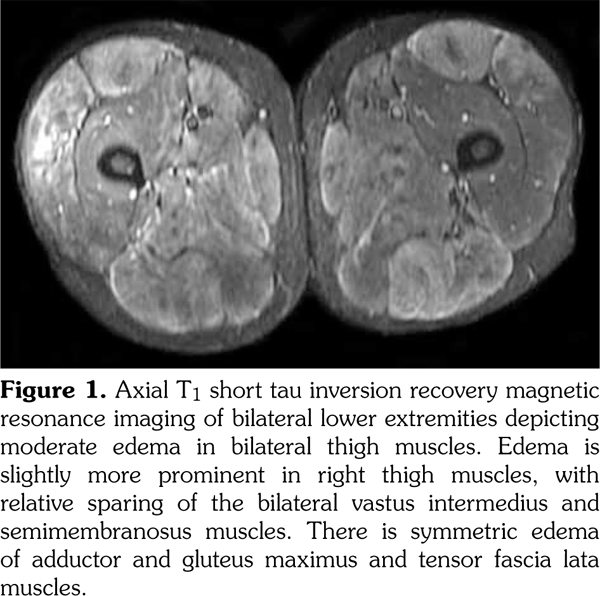

A biopsy of quadriceps muscle demonstrated active myopathic changes and perivascular and endomysial mononuclear focal inflammatory infiltrate (Figure 2). No rimmed vacuoles or abnormal accumulation of lipids or mitochondria were identified. The immunohistochemical staining for major histocompatibility complex class 1 was equivocal. Histochemical stains showed normal myophosphorylase, phosphofructokinase and myoadenylate deaminase, succinate dehydrogenase, nicotinamide adenine dinucleotide + hydrogen and cytochrome oxidase activity. These findings confirmed the diagnosis of polymyositis.